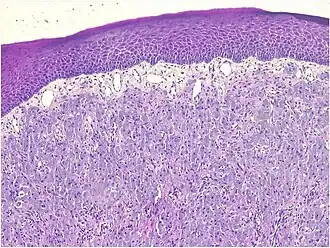

Histopathological Characteristics

Histopathologically, congenital epulis is usually characterized by the presence of big, rounded cells that fill the mucosa's lamina propria and have round to oval nuclei and an abundance of eosinophilic cytoplasm.[10] A thin layer of connective tissue separated the surface layer of cells from the growing new cells. Numerous histological traits, such as a fibrous and granulomatous appearance, have been reported in recent research.[10]

Microscopically, congenital epulis is composed of:

- Sheets of proliferating polygonal to round cells with overlying thin squamous, eosinophilic, granular cytoplasm[12][13]

- Centrally located, round nuclei [7]

These histopathological features are essential in distinguishing congenital epulis from other gingival and soft tissue neoplasms.